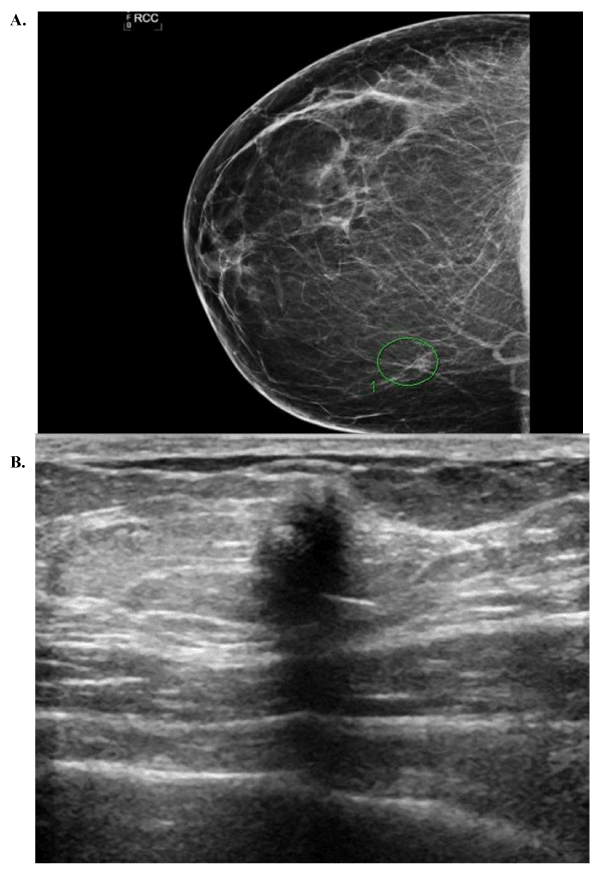

Seven patients with GCT were identified from the pathology database over the allotted time period. Pathological review classified all tumors as benign. Patient demographics, imaging characteristics, tumor size, and margin status can be found in Table 1. All patients were of African American descent between the ages of 20 and 58. There was one male patient who did not have preoperative imaging and was lost to follow up after excision. Six patients had preoperative breast imaging; 4 had both digital mammography and biphasic ultrasound examinations and 2 had only biphasic ultrasound examination. The majority of masses had distinct radiographic characteristics; spiculated margins, posterior acoustic shadowing, and no calcifications present (Figure 1). All images were characterized as either BI-RADS 4 or 5. All but one patient with preoperative imaging had a preoperative core needle biopsy consistent with benign granular cell tumor. Six cases were solitary; and one patient having multi-centricity with masses in the breast and ipsilateral axilla. All masses were removed via lumpectomy or wide excision. The tumors had a mean size of 1.5 cm. Two patients had close margins and two others had positive margins. There were no recurrences, or abnormalities found on breast imaging, in the cohort with mean follow up time at 44 months (range 3-129 months).

Figure 1. (A) Mammogram depicting mass without calcifications, (B) Ultrasound of a breast mass with spiculated margins and posterior acoustic shadowing